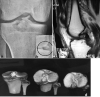

Objective: to assess twenty two cases of isolated PCL avulsion fractures from tibial insertion, arthroscopically treated with suture pull technique, and to evaluate achieved clinical outcomes in terms of radiographic laxometry (objective) and Lysholm scale (subjective).

Material and method: Study includes 22 cases operated between April 2014 and March 2017. Patients less than 18 years old, presentation after 3 weeks of injury, concomitant injury in the same limb, with open wounds or with comminuted avulsed fragment were excluded from the study. All cases were MRI proven. All arthroscopic suture fixation technique was used in all cases. Follow up was done at 3 weeks, 6 weeks, 3 months, 6 months and 12 months. Mean follow up was one year. Subjective complaints, Knee flexion, Lysholm score and stress radiographs were noted.

Results: Average Lysholm score was 96.3. Seventeen patients had excellent results and Five had good results based on Lysholm scores. In two patients, grade 2 laxity (5-10 mm) was present on stress radiographs but there were no clinical complaints. All patients achieved osseous union and had no functional limitation. Three Patients developed arthrofibrosis initially but gained functional range later.

Conclusion: Arthroscopic suture fixation method for PCL avulsion fracture from tibia is a good and safe method of choice for fixation.